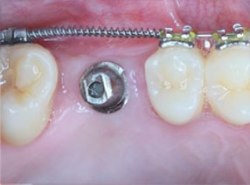

植牙治療過程

治療中

治療後